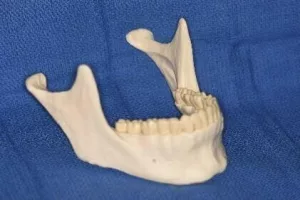

L’os basal

L’os basal constitue la base architecturale des mâchoires ; la mandibule en bas et le maxillaire en haut. Stable, très solide, majoritairement compact, indépendant des dents et de l’os alvéolaire, il reste présent tout au long de la vie. En cas d’édentement complet et après une longue période d’involution de l’os alvéolaire, seul subsiste l’os basal. Ce phénomène touche autant la mandibule que le maxillaire supérieur